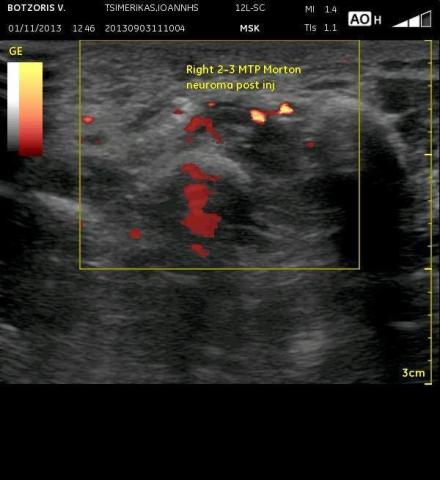

Το νευρίνωμα του Morton αποτελεί συχνό αίτιο πόνου στο άκρο πόδι -μεταξύ των μεταταρσίων- συχνά δε διαλάθει της προσοχής και της διάγνωσης με συνέπεια οι ασθενείς να ταλαιπωρούνται για καιρό με πόνο που τους ενοχλεί στο βάδισμα και την όρθια στάση κυρίως.

Με τον υπέρηχο επιτυγχάνεται σε μεγάλο ποσοστό έγκυρη διάγνωση (και έγκαιρη αν κλινικά κινήσει την υποψία του γιατρού), ενώ υπάρχει και η δυνατότητα κατευθυνόμενης έγχυσης κορτιζόνης γύρω από το νευρίνωμα με πολύ καλά ποσοστά επιτυχίας και επακόλουθη ανακούφιση του ασθενούς.

Νευρίνωμα του Morton